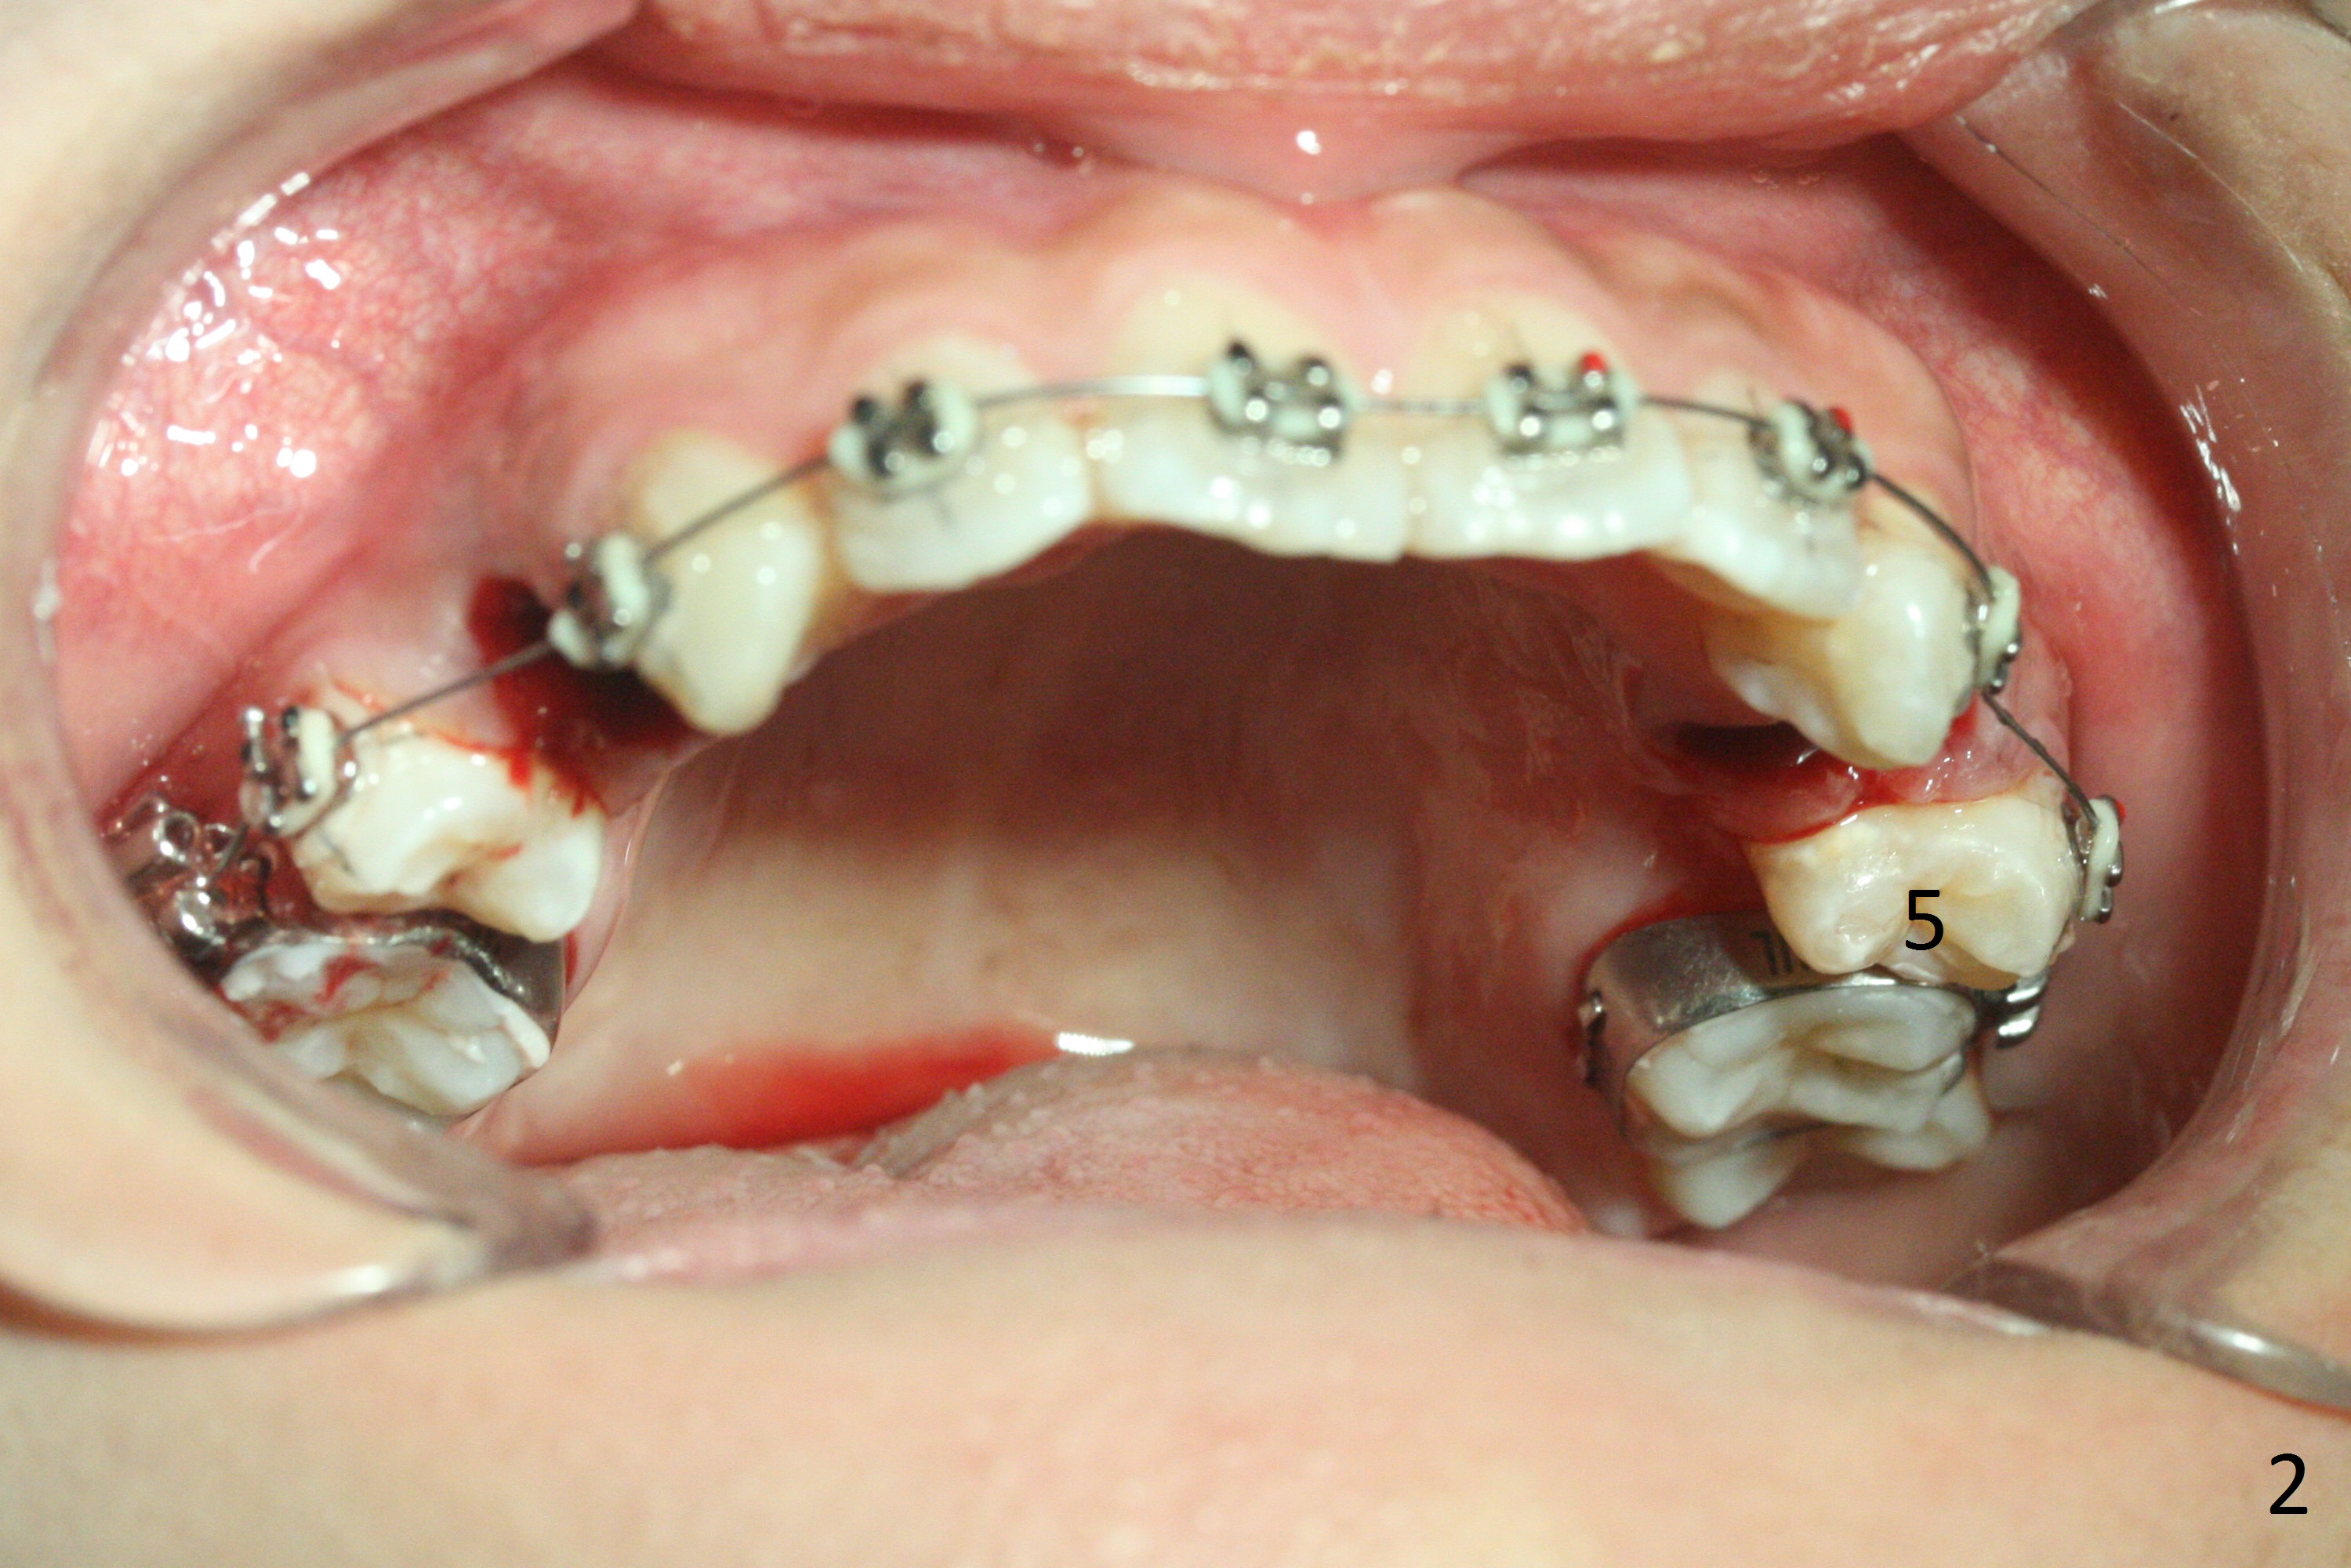

When the 17-year-old woman returns for banding, she has no problem with extraction (Fig.1). Since UL5 is buccally displaced, it is extremely difficult to insert .012 niti wire into the 1st molar band when the lower tube slot is smaller (apparently .018 instead of .022, Fig.2). Do not remove the thin niti wire before the bicuspid is linguolized.

For the lower left quadrant, a band is placed at 7, but not at 6, since the space between 5 and 6 is not enough. A new separator is placed between 6 and 7, while power chains are placed between 3 and 5 (Fig.3). The patient will return for banding at 6 next week.